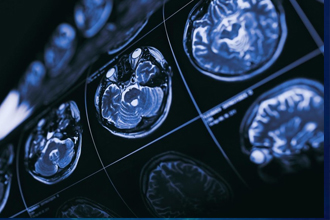

在太空旅行的早期,科学家们努力研究如何克服重力,使火箭能够不受地球引力的影响而把人类送上月球。如今,重力仍然是科学议程的重中之重,但这次我们更感兴趣的是重力的减弱如何影响宇航员的健康,尤其是他们的大脑。毕竟,我们已经进化到在地球引力(1倍重力)下生存,而不是在太空失重(零重力)或火星微重力(0.3倍重力)条件下生存。

那么,人类大脑究竟是如何应对微重力影响的呢?糟糕的是,大脑被保护在“坚果壳”中,关于这方面的信息非常有限。不过我们知道,宇航员在失重时的脸会变得红肿,这种现象被亲切地称为“查理-布朗效应”(Charlie Brown effect),或者“肿头鸟腿综合症”。这是因为,大部分由血液(细胞和血浆)和脑脊液组成的液体向头部移动,导致他们脸部变得圆胖,腿部则变得纤瘦。

这些液体流动也与太空运动病、头痛和恶心有关。最近,由于血流增加,大脑在颅内向上漂浮,导致血压升高,视力模糊也与此有关,这种情况被称为视力障碍和颅内压综合征。尽管美国宇航局认为这种综合症是任何火星任务的首要健康风险,但要弄清楚导致这种症状的原因,以及如何预防它,仍然是个谜。

对此,南威尔士大学生理学和生物化学教授达米安·贝利(Damian Bailey)认为,大脑的某些部分最终接受了太多的血液,因为一氧化氮(通常漂浮在血流中但却看不见的分子)在血液中积聚。这使供应大脑血液的动脉放松,从而使它们过度扩张。由于血流量激增,血脑屏障(大脑的“减震器”)可能会不堪重负。这使得水慢慢积聚(即出现所谓的水肿),导致大脑肿胀和压力增加,这也可能由于排水能力受限而变得更糟。

贝利的初步发现证实了先前的预期。在体验反复失重后,一氧化氮水平会上升,这与血液流动增加相一致,尤其是通过供应大脑后部的动脉。这迫使血脑屏障打开,尽管没有证据表明产生结构性脑损伤。贝利等人现在正计划在这些研究的基础上,利用磁共振等成像技术对大脑中的血液和液体流动进行更详细的评估,以证实他们的发现。